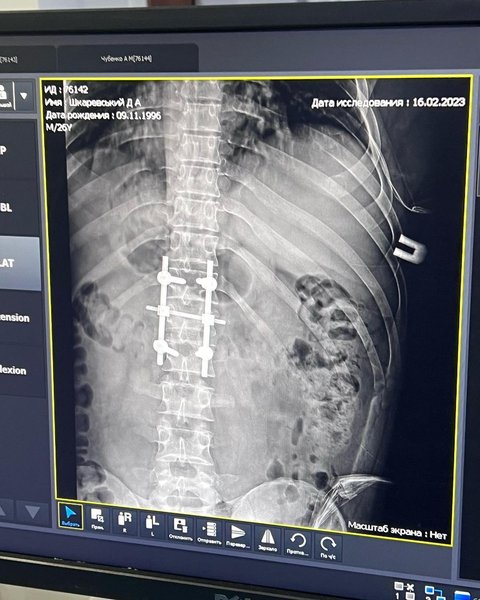

В больнице Дмитрию Шкаревскому поставили диагноз — перелом позвонка в поясничном отделе и многочисленные обсколочные ранения.

Пилоту в больнице сделали операцию и установили титановый каркас на позвоночнике, благодаря которому он уже через месяц встал на ноги. Теперь в шутку Дмитрий называет себя "терминатором".